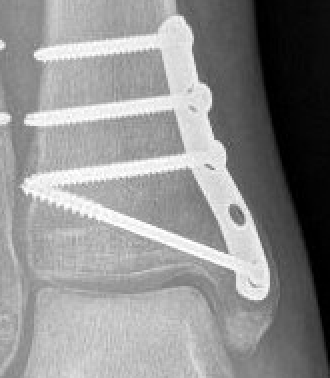

Fixation options

| Screw fixation | Tension band wire | Buttress plate |

|---|---|---|

| Type C: transverse fractures |

Type B: too small for two screws |

Type D: Vertical fractures |